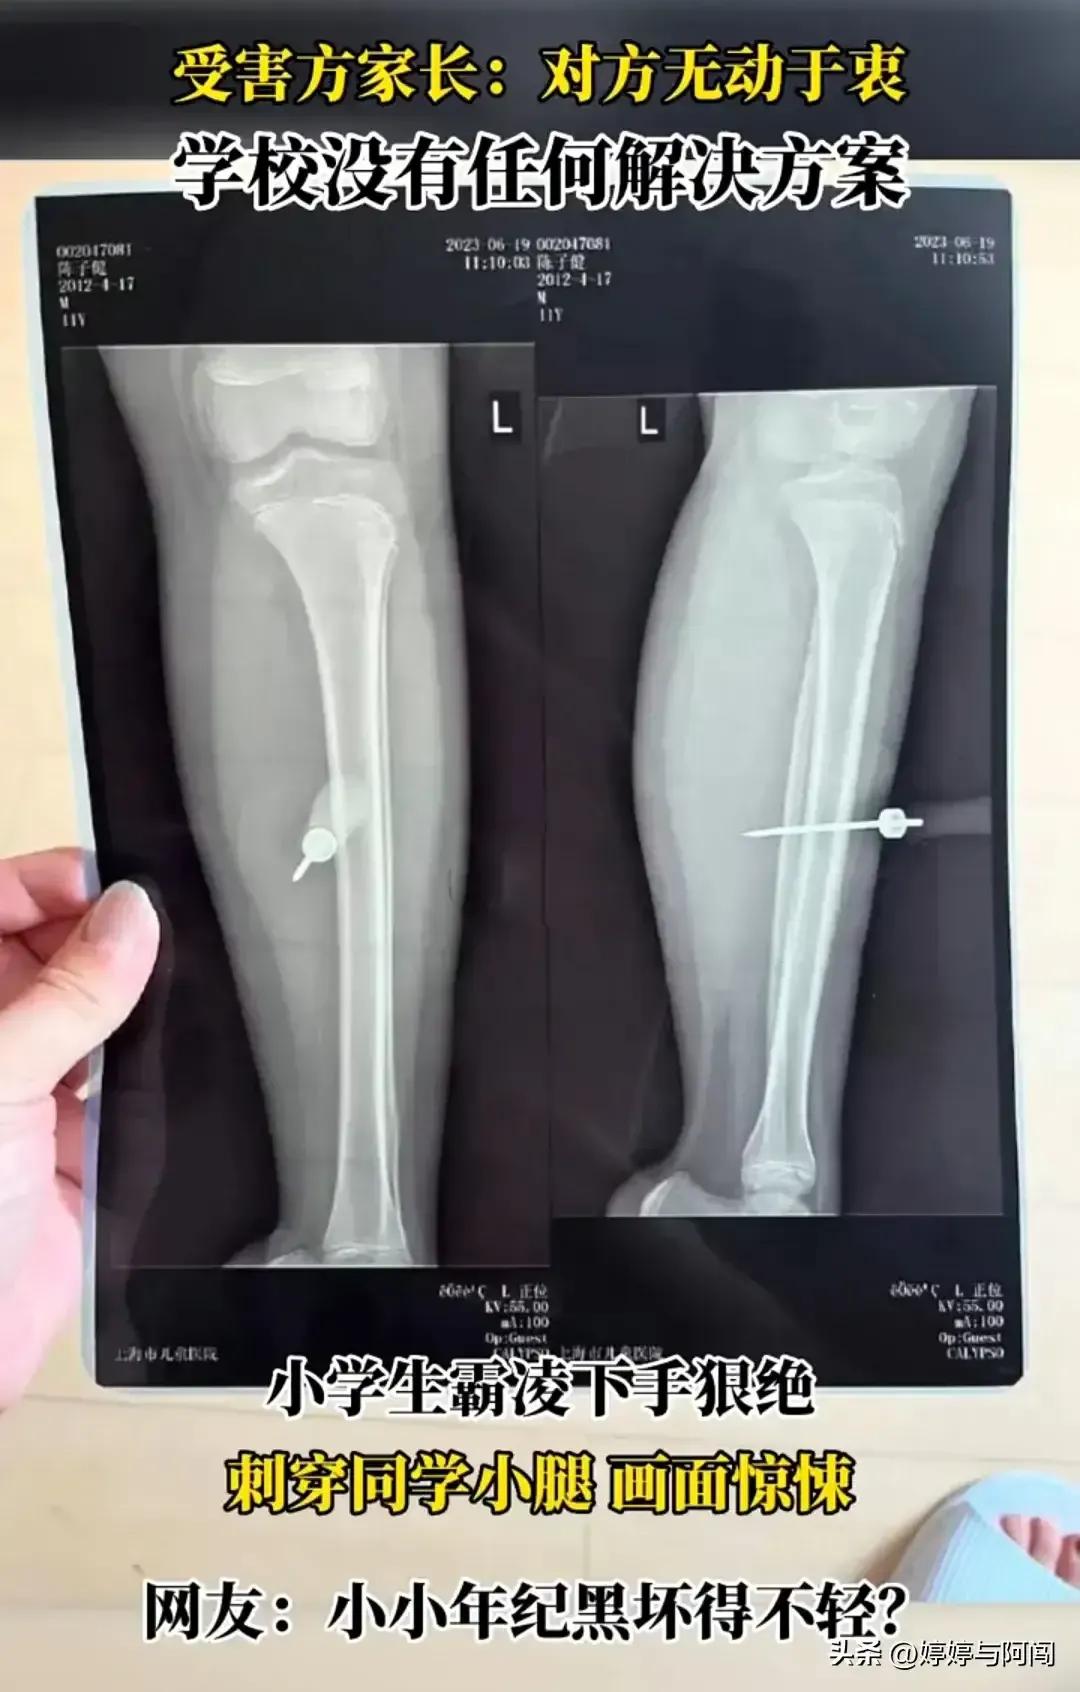

从医院的X光片上也清楚的看到整个铁锥一捅到底,伤势非常严重,医生要求马上手术,全麻手术后,已经住院进一步观察。